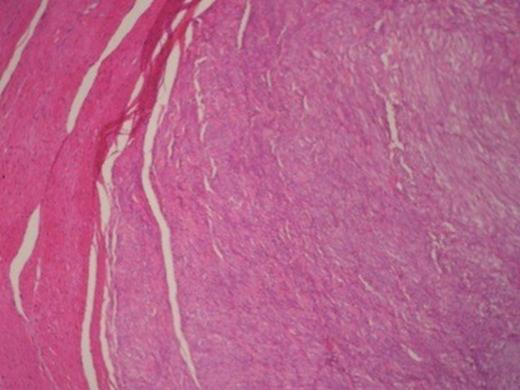

Histologically, the tumour was composed of fibroblasts that were arranged vertically. Smooth muscle cells were also recognized that apparently were remnants of the mucosal muscle layer. Also, redundant confluent lymphocytes, plasmocytes, mast cells with rare giant cell forms, as well as redundant eosinophilic granulocytes were recognized. The supernatant mucous membrane showed signs of active inflammation, and in the area of the crater, a healed ulcer was recognized. The final pathologic diagnosis was consistent with IMT that originated from the gastric wall (Figure 3).Gross examination of the nodule from the anterior wall of the fundus of the stomach showed a whitish gray elastic mass measuring 1.5x1x1cm. The tumour was identified as an incipient gastrointestinal stromal tumour that consisted of uniform neoplastic cells without nuclei atypia ((Figure 4).The node from the superior hepatic surface was identified as a syringious haemangioma. The dimensions of the haemangioma were 2x1.5x1cm and the tumour had chestnut complexion and friable texture ((Figure 5).

Gastrointestinal stromal tumour in the right and smooth muscle cells in the left.